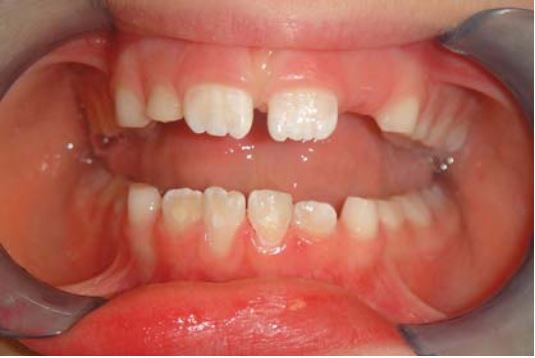

Sau khi răng cửa bị gãy thì nên giữ lại phần gãy trong nước hoặc khăn giấy ẩm để tránh mảnh răng bị khô, gây mất thẩm mỹ và khó kết dính (Sharmin, 2013) (H18.2).

Nếu gãy vát về phía cổ thì giúp tăng khả năng dán và tăng diện tích bề mặt dán (H18.4).

Gắn lại mảnh gãy răng cửa hàm dưới thường khó vì kích thước rất nhỏ (H18.14).